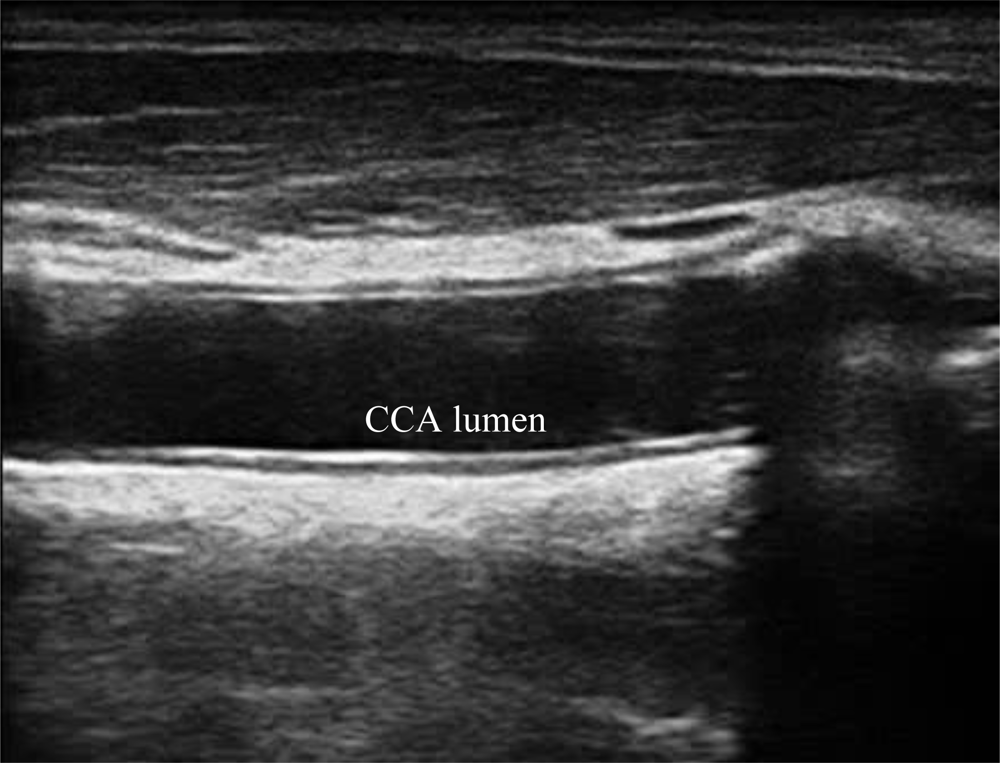

A typical B-mode image is shown in Figure 1. There are plaques on both near and far walls. On the contrary, a typical CCA image without plaque having thin and thick IMT is shown in Figures 2 and 3, respectively. Outlining the boundaries of intima and adventitia is not easy, especially on the near wall. Some features have been studied in previous studies [7,11], in which the most frequently used feature is the gradient of gray-values. From our previous studies [7,14,17], it is found that MacLeod operator combined with some specific enhancement filters are very suitable for feature extraction in intima and adventitia detections.